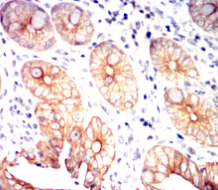

IHC    1/100 - 1/500